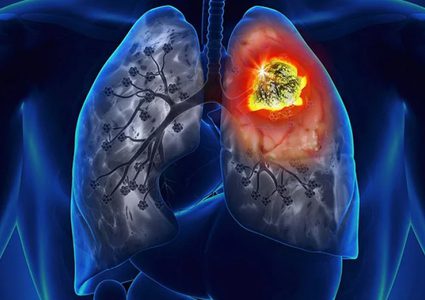

يرتبط سرطان الرئة بشكل وثيق مع التدخين، ولكن نسبة الإصابة به ارتفعت بشكل ملحوظ بين أوساط النساء، بينما تتراجع سنويا عند الرجال. وتزداد أعداد النساء المصابات …

قبل الإقدام على خطوة تلقي علاج سرطان الرئة، يحدد الأطباء بعد التشخيص العلاج الآمن والفعال حسب كل حالة ومراحل تقدم المرض. ووفقاً لموقع " cancer" المتخصص …

الرئة تزوّد الجسم بالأوكسيجين الذي تحتاجه الخلايا، والتخلص من ثاني أكسيد الكربون والملوثات. في ما يلي بعض النصائح للمحافظة على الرئة بصحة جيدة أطول فترة …